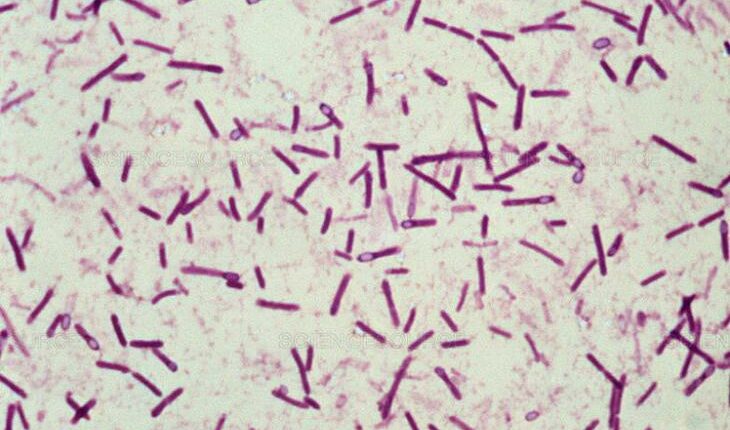

1. Clostridium botulinum

Эта бактерия вызывает ботулизм — тяжелое заболевание, поражающее нервную систему человека. Больные ботулизмом погибают, как правило, от паралича дыхательной мускулатуры и последующей гипоксии. Считается, что чайной ложки ботулины достаточно, чтобы уничтожить население США. А 4 кг хватит на истребление всех жителей планеты.